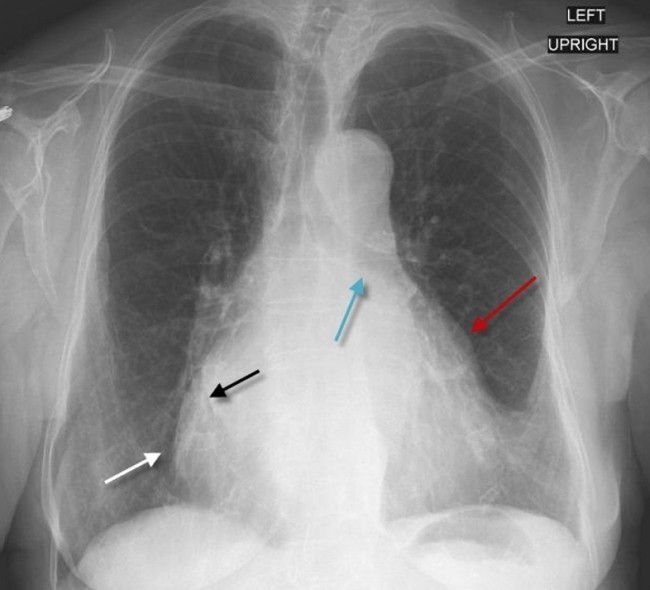

심첨부에서 들리는 low pitch rumbling murmur, 제1심음 강화, 제2심음 분리는 승모판협착증을 암시하는 소견들입니다. 또한 mitral stenosis(MS)에서 가장 흔하고 중요한 비정상 심전도는 심방세동이며 다른 심전도 소견들은 MS에 특이적이지 않습니다. 추가로 언급한다면 left atrial hypertrophy와 enlargement로 인한 lead V1 : biphasic P파, lead II : broader (duration in lead II >0.12 sec), P-mitrale 입니다. 하지만 AF으로 인하여 P파의 변화가 분명하게 보이지 않을 수도 있습니다. 폐동맥 고혈압과 우심실비대가 생기면 frontal axis가 우측으로 이동하고(S>R in lead I and aVL), tall R wave가 V1, V2에서 보입니다(R>S or R/S ratio >1). Mild MS에서 흉부엑스레이는 일부에서 left atrium과 appendage의 약간의 enlargement를 보일지라도 보통 정상입니다. Left atrial enlargement는 double density와 left heart border의 직선화를 나타냅니다.

Red arrow : The left atrium is enlarged, displacing the left atrial appendage outward

Black arrow : "Double density" consisting of overlapping of the left atrium

White arrow : Right atrium

Blue arrow : The left main bronchus is elevated by the enlarged left atrium pushing it upwards